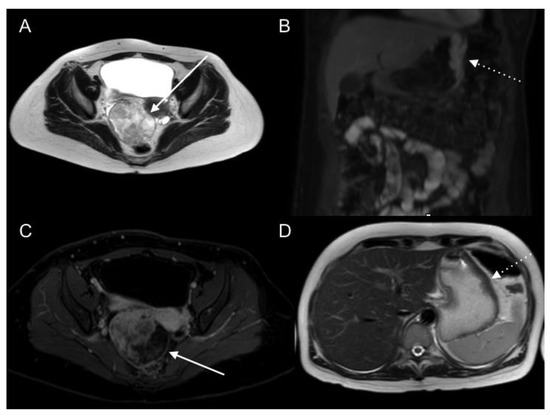

- Espada, M.; Garcia-Flores, J.R.; Jimenez, M.; Alvarez-Moreno, E.; De Haro, M.; Gonzalez-Cortijo, L.; Hernandez-Cortes, G.; Martinez-Vega, V.; Sainz De La Cuesta, R. Diffusion-weighted magnetic resonance imaging evaluation of intra-abdominal sites of implants to predict likelihood of suboptimal cytoreductive surgery in patients with ovarian carcinoma. Eur. Radiol. 2013, 23, 2636–2642. [Google Scholar] [CrossRef] [PubMed]

- Fujii, S.; Matsusue, E.; Kanasaki, Y.; Kanamori, Y.; Nakanishi, J.; Sugihara, S.; Kigawa, J.; Terakawa, N.; Ogawa, T. Detection of peritoneal dissemination in gynecological malignancy: Evaluation by diffusion-weighted MR imaging. Eur. Radiol. 2007, 18, 18–23. [Google Scholar] [CrossRef] [PubMed]